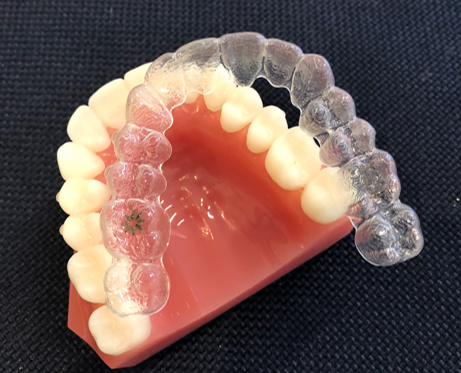

矯正治療でよく使われるはり金の装置は目立ってしまいます。 当院では、こども専用の取り外し式のマウスピース型装置を用います。 装置を使うのはご自宅で起きている時の1時間と夜寝ている時です。 学校につけていく必要が無いので、周りの人に気づかれずに治療を進められます。

取り外し式のマウスピース型装置はシリコン製で柔らかいです。 痛みを感じることはほとんどありません。

オーストラリア発祥の世界的な矯正グループであるマイオブレースメンバーに加盟しています。 こどもの矯正では世界最大級のグループです。 今や世界中のこどもたちがこのマイオブレース矯正治療を受けています。 そのシステムに沿った安心安全でかつ信頼できる治療を心がけています。 マイオブレースメンバーに加盟して正規でこの治療法を提供しているのは札幌では当院を含めたったの2医院です。

マイオブレース治療を厳守しながら必要な場合にはバイオブロック治療やその他の方法も提案します。 その子にとって最も最適な方法を最適な時期を選択して治療していきます。